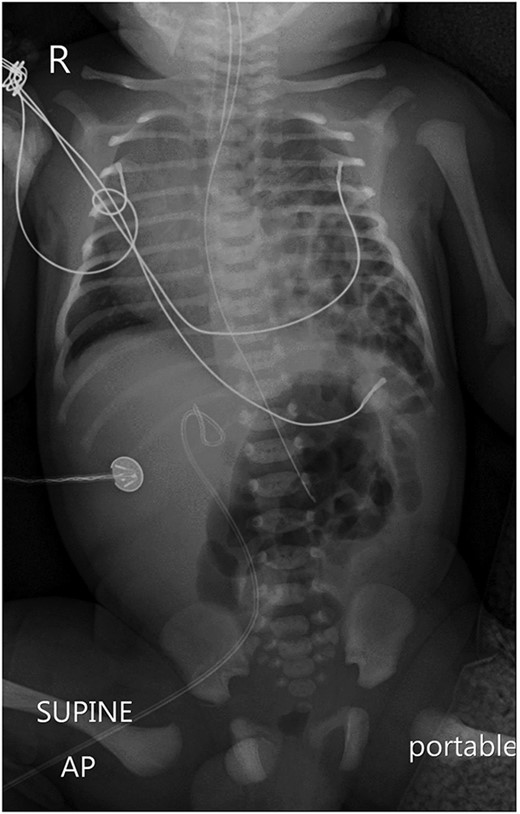

Postoperatively, a chest X-ray revealed a small left-sided pneumothorax that resolved in a few days (Fig. 2). Three days after the surgery, the fentanyl infusion was stopped, and the patient was extubated to a high-flow nasal cannula for 5 days. On the same day, the patient was noted to have a greenish-yellow aspirate. The patient was febrile the day after, a septic screen was done, and the patient was treated with ceftriaxone and vancomycin for 2 weeks. Furthermore, the surgical site was noted to have purulent discharge, for which fusidic acid was locally applied for 2 weeks. Abdominal ultrasound conducted a week after surgery showed an oval collection of fluid with intrinsic echoes, possibly a splenic hematoma, in the left upper quadrant, which was self-limited after 2 months of follow-up (Fig. 3). Before discharge, the patient’s parents were advised on a nursing plan, oral sucrose for analgesia and ranitidine.

Abdominal ultrasound conducted 1 week post-operatively showed a possible splenic hematoma, which was self-limiting.